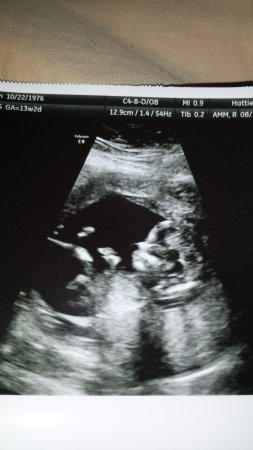

13w2d nub..any guesses?

13w 2 d NT scan...Thanks for looking!